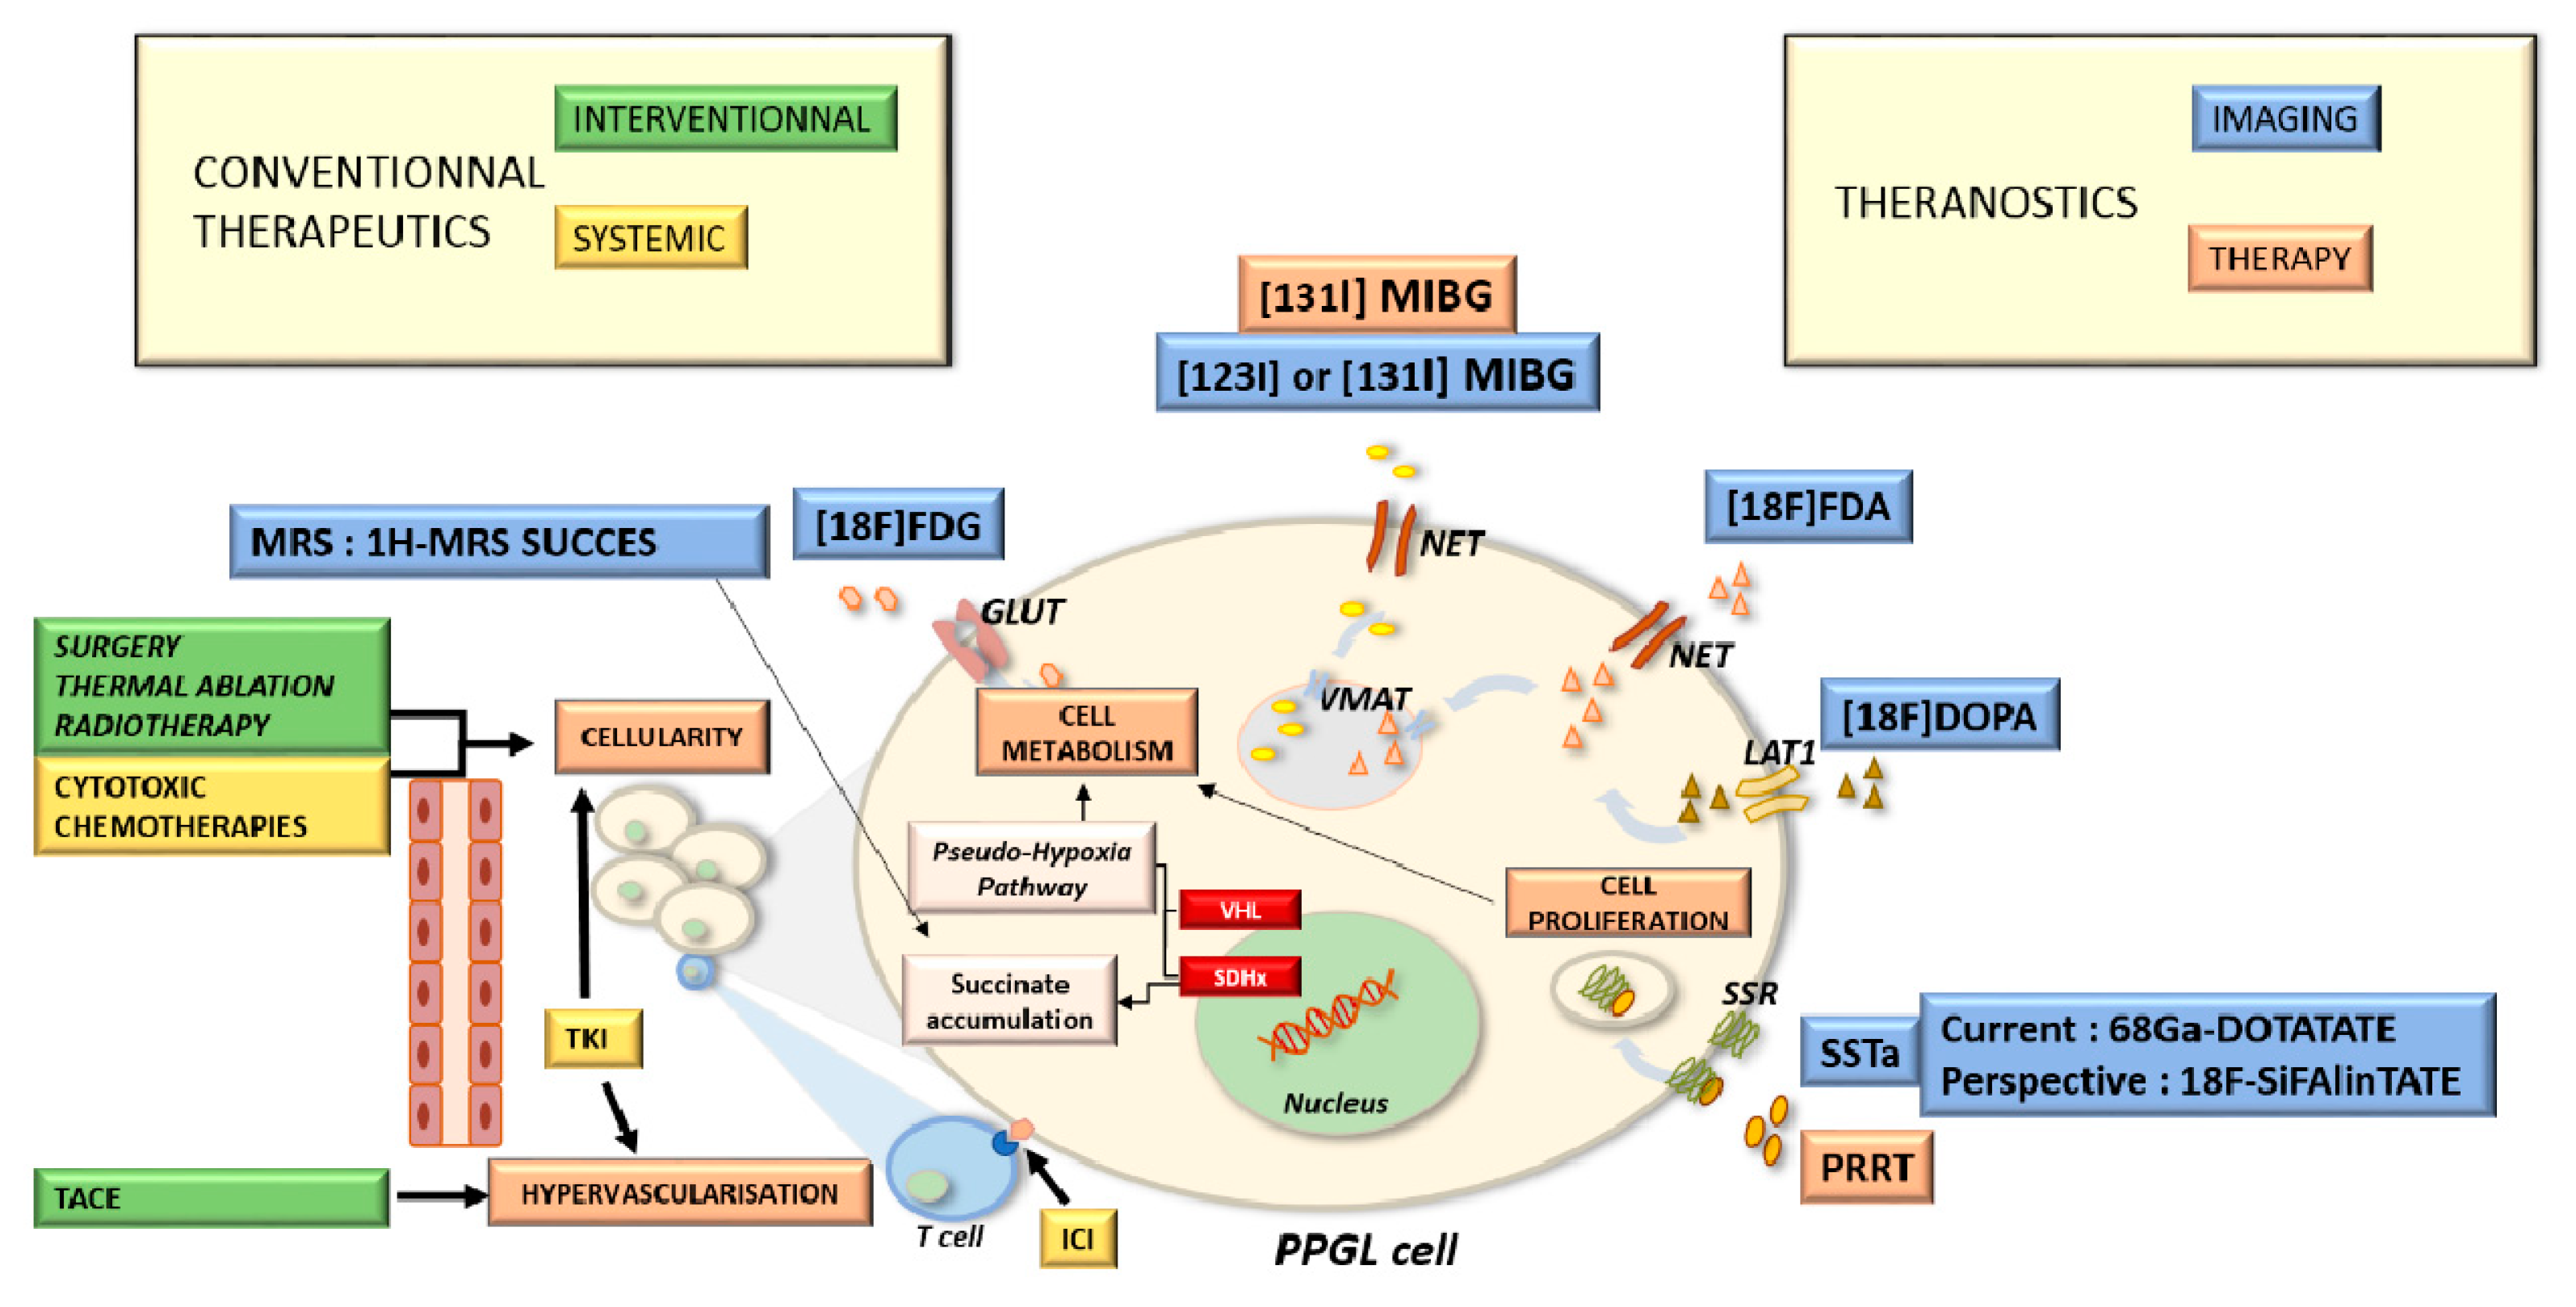

6. Imaging Guided Therapeutic Options

7. Systemic Therapies: Impact of New Therapeutics in Imaging Management

8. Targeted Radionuclide Therapies in Palliative Treatments

8.1. Rationale

8.2. Iobenguane

8.3. Peptide Receptor Radiotherapy

9. Tumor Response Management: New Concepts and Pitfalls

4. Molecular Imaging Techniques in Precise Diagnosis and Follow-Up

4.1. Metaiodobenzylguanidine: About the Historical Tracer

4.2. Contributions of Computed Tomography Using Dopamine and Glucose Analogues

4.3. Positron Emission Tomography with Computed Tomography Using Somatostatin Analogues

4.4. Current Guidelines for Molecular Imaging in Diagnosis and Staging of PPGLs